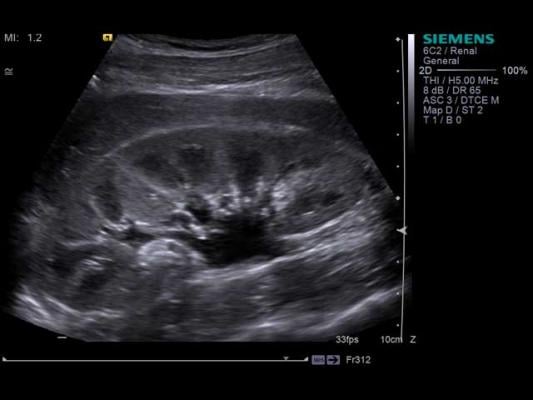

He examined 24 ESKD patients at Augusta University Health. As part of the normal physical exam, he placed the ultrasound probe on the patients' chests to get a good view of the lungs. If there was fluid, he would see B-lines, which are actually reflections of the water in the lungs that appear as long, vertical white lines on an ultrasound. The higher the number of B-lines and the more intense, or bright, they were, the more fluid was present.